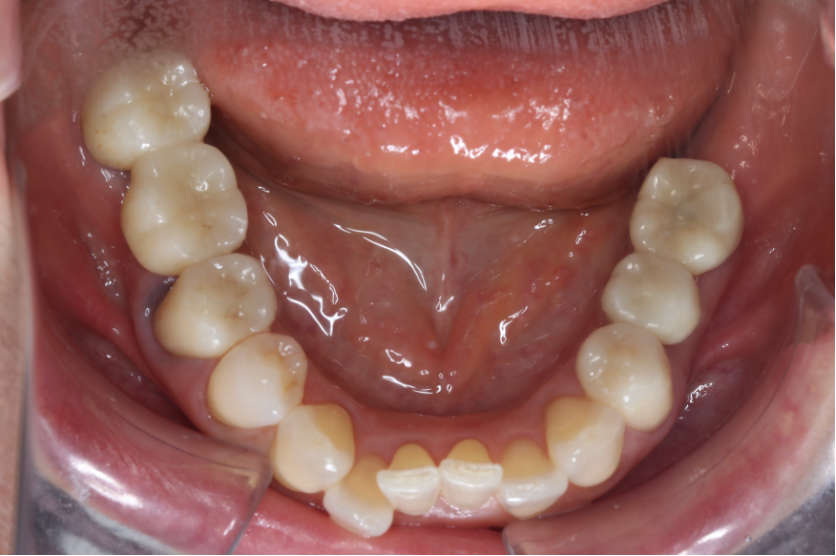

セラミック症例①

年齢40代女性

治療期間1ヶ月

治療内容ジルコニア、セラミックインレー、セラミッククラウン

治療箇所左上1番、2番 左下5番、7番 右上1番、2番、3番、4番、5番 右下5番、6番、7番

治療費用100,000円